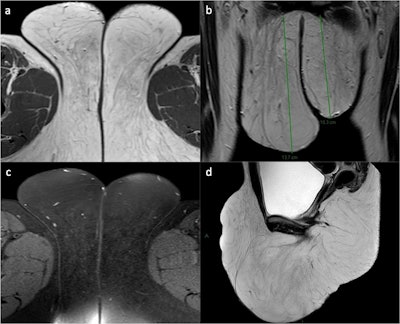

Childhood asymmetrical labium majus enlargement (CALME). A 30-year-old woman presented with hypertrophy of the external genitalia without skin alterations or symptoms. Axial (a), coronal (b), and sagittal (d) T2WI reveal hypertrophic subcutaneous adipose tissue (both superficial and deep) in the vulvar area, particularly at the level of the mons pubis and the labia majora (right > left). Axial fat-saturated T2WI (c) confirms adipose hypertrophy without signs of heteroplastic tissue or lymphoedema. The final diagnosis was late-onset CALME.